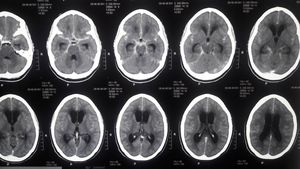

CT-Brain

There are basal enhancements seen on the contrasted CT in an asterix/ star shape. Dilated ventricles with periventricular hypodensity indicating ongoing inflammation. These findings together with the history tells us that it is TB meningitis